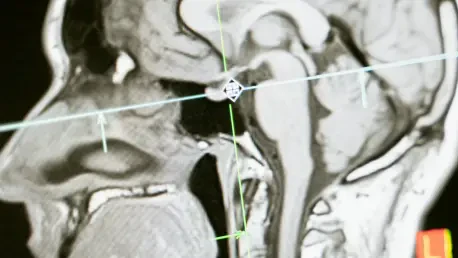

The development of the BSBT algorithm hinged on overcoming long-standing imaging challenges through the sophisticated application of artificial intelligence, specifically a type of AI model called a “convolutional neural network” (CNN). This advanced network was designed to analyze data from diffusion MRI, a specialized imaging technique that traces the movement of water molecules as they travel along the long, myelinated branches of neurons, known as axons. The process began by first generating “probabilistic fiber maps,” which outlined the likely trajectories of the major white matter pathways descending into the brainstem from higher brain regions like the thalamus and cerebellum. The CNN then integrated these probabilistic maps with multiple channels of direct imaging information sourced from within the brainstem itself. By expertly combining these disparate data sources, the network learned to accurately distinguish and segment eight individual fiber bundles, a task that was previously impossible to automate with such precision. This intricate, multi-stage approach equipped the AI with the nuanced capability to identify these critical structures automatically, effectively creating a high-definition roadmap of the brainstem’s internal wiring from standard clinical scans.

With its accuracy firmly established, the BSBT was applied to extensive datasets of diffusion MRI scans from patients with a range of neurological conditions, marking a pivotal transition from a research tool to a potential clinical powerhouse. The algorithm was used to measure two key metrics: the volume of each white matter bundle and its “fractional anisotropy” (FA), a value that reflects the structural integrity of the nerve fibers. High FA values indicate healthy, well-organized axons, while a reduction suggests damage, degradation, or disease. The study yielded several remarkable findings that demonstrated distinct patterns of structural change specific to each condition. For instance, in patients with Parkinson’s disease, BSBT revealed a significant reduction in FA in three of the eight identified bundles and detected a loss of volume in another bundle when comparing baseline scans to follow-ups conducted two years later. In contrast, patients with multiple sclerosis exhibited the most pronounced FA reductions across four specific bundles, along with volume loss in three. These detailed, quantitative assessments provide a powerful adjunct to current diagnostic imaging, offering structural and longitudinal information that was previously inaccessible and paving the way for more precise diagnoses.